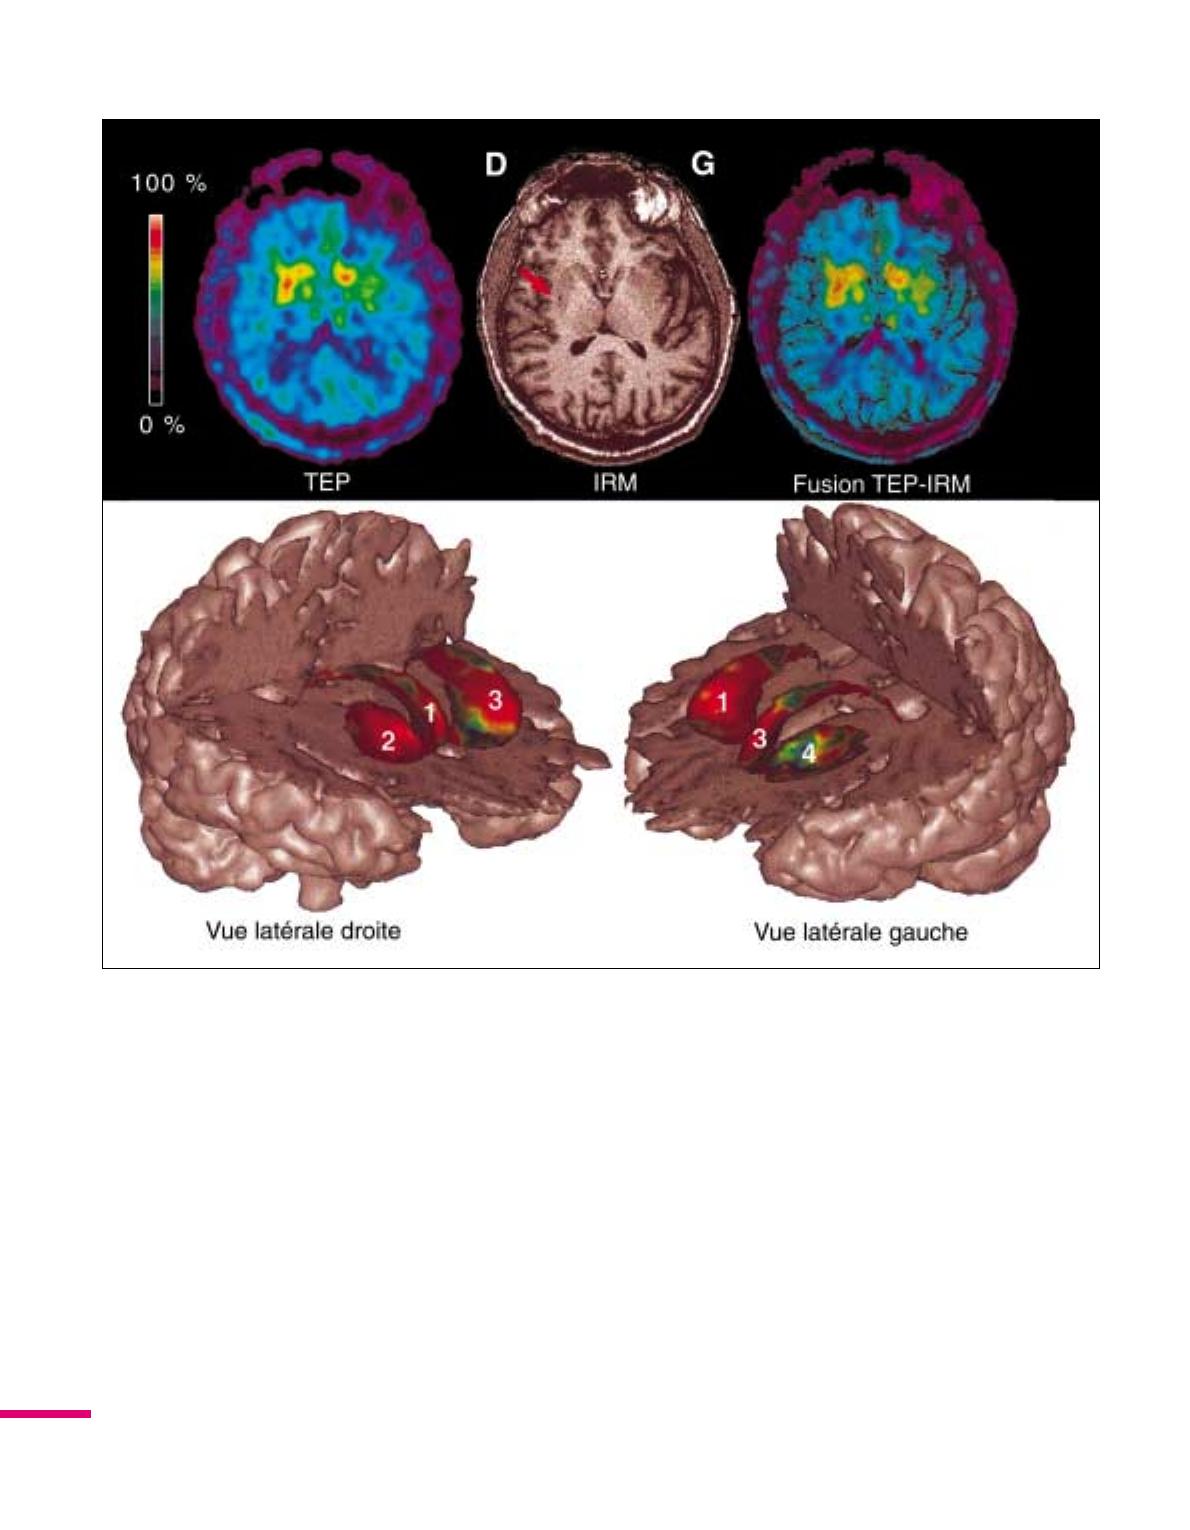

Le développement des techniques

dimagerie devrait permettre de

mieux analyser les relations existant

entre la topographie de cette réinner-

vation dopaminergique du striatum et

l’évolution clinique des malades. Cela

pourrait être fait, par exemple, en

fusionnant les images fonctionnelles

(TEP) et anatomiques (IRM) obte-

nues chez le même patient (figure 3).

En effet, cette fusion permet de déter-

miner avec une plus grande précision,

et en trois dimensions, les relations

anatomiques existant entre la restau-

ration de la fonction dopaminergique

striatale et les implants cellulaires.

Figure 3. Fusion IRM-TEP chez un malade parkinsonien greffé.Ce patient a été greffé dans le putamen droit (à

gauche sur les images). On voit sur la coupe IRM le puits de descente de laiguille pour limplantation des cellules

dans le putamen. À côté, limage TEP au même niveau montre le captage du traceur plus marqué du côté greffé. En

dessous, limage de fusion TEP-IRM en 3 dimensions obtenue grâce à un logiciel développé dans notre institut (J.-F.

Mangin et F. Poupon, CEA Orsay). Seul le captage striatal du traceur est représenté dans chacun des hémisphères :

lhémisphère droit est à gauche avec le noyau caudé (1) et le putamen (2), qui est le siège de la greffe; lhémisphère

gauche est à droite avec le noyau caudé (3) et le putamen (4). On constate que le captage du traceur dans le noyau

caudé (3) est relativement préservé par rapport à celui du putamen (4) à gauche. Cet aspect est habituel dans la

maladie de Parkinson. À linverse, du côté greffé, le captage du traceur dans le putamen (2) est augmenté, atteignant

les valeurs de celle du noyau caudé (1). D : droite; G : gauche.